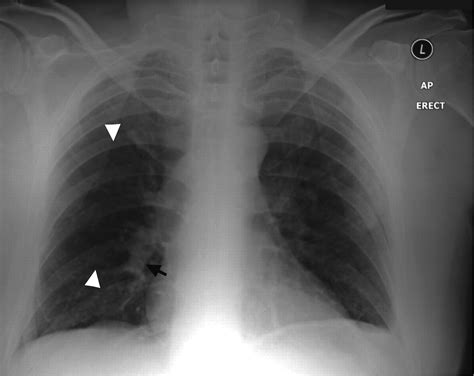

Key findings on a Pulmonary Embolism X Ray that may suggest PE include:

• Wedge-shaped opacities: These are areas of increased density in the lung tissue, often seen in the periphery of the lung.

• Pleural effusion: Fluid accumulation in the pleural space, which can be a sign of inflammation or infection.

• Enlarged pulmonary arteries: Dilatation of the pulmonary arteries, which may indicate increased pressure due to a clot.

• Atelectasis: Collapse or incomplete expansion of the lung tissue, which can be a sign of obstruction.

However, it is important to note that these findings are not specific to PE and can be seen in other conditions. Therefore, further diagnostic testing is often required to confirm the diagnosis.